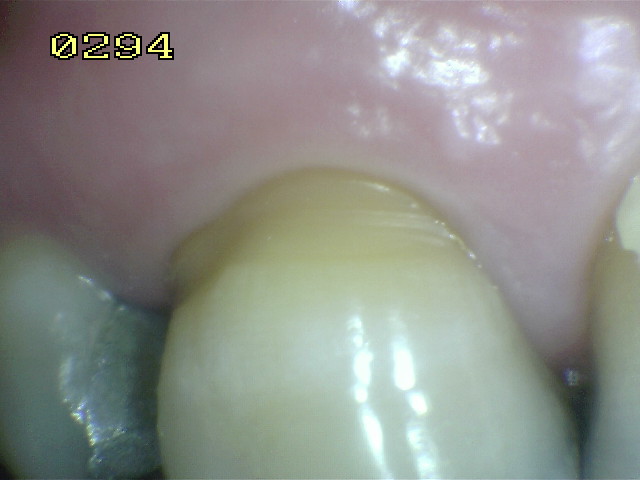

Código 0: La superficie de la raíz no presenta ninguna coloración inusual que lo distingue de los alrededores o las áreas adyacentes de la raíz, ni exhibir un defecto de la superficie, ya sea en la unión cemento-esmalte o totalmente en la superficie de la raíz. La superficie de la raíz tiene un contorno anatómico natural. Ver imagen inferior.